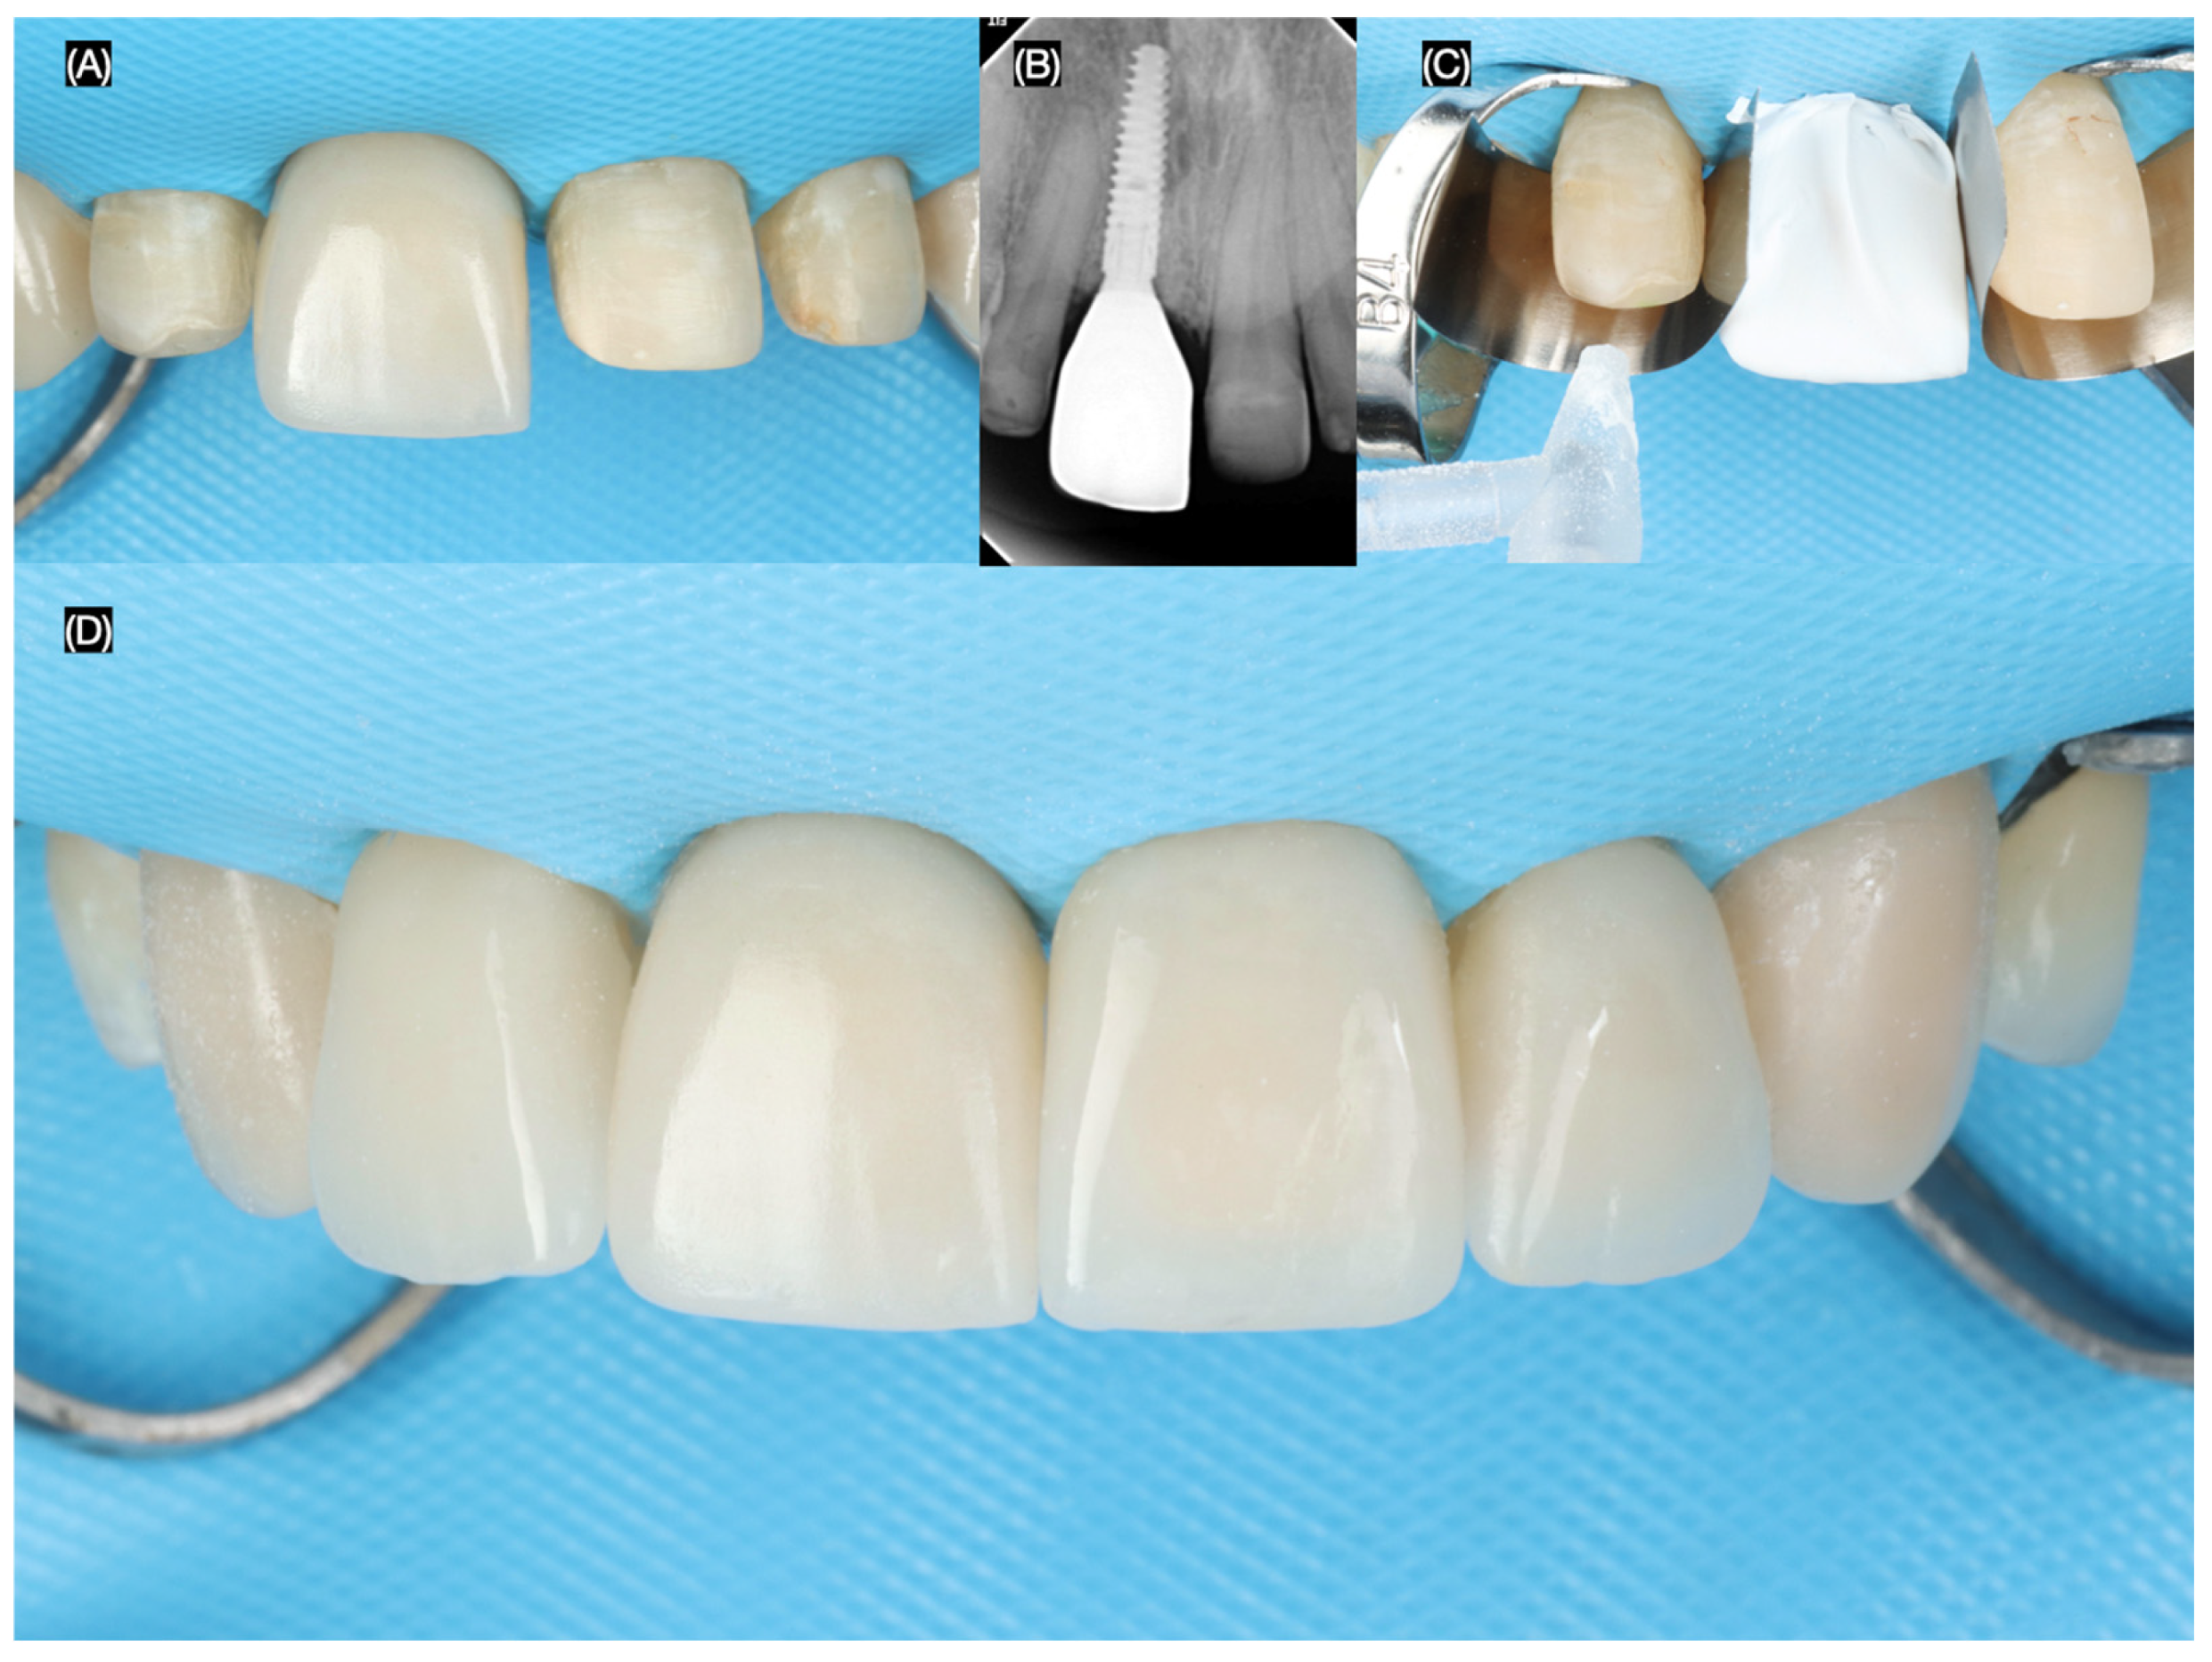

The final screw-retained implant crown was placed, ensuring proper fit, occlusion, and esthetics. A dental dam was then applied to achieve total isolation for the cementation of the veneers, ensuring a clean and controlled environment. The tooth surfaces were first prepared using sandblasting, followed by etching with phosphoric acid. The lithium disilicate veneers were treated with hydrofluoric (Porcelain Etchant, Bisco, Schaumberg, IL, USA) acid for 20 s, thoroughly cleaned in an ultrasonic water bath for 5 min, and coated with a silane (Porcelain Primer, Bisco, Schaumberg, IL, USA) coupling agent for 60 s. Finally, the veneers were bonded using universal adhesive (All Bond Universal, Bisco, Schaumberg, IL, USA) and dual-cure resin cement (Choice 2 Veneer Cement, Bisco, Schaumberg, IL, USA), ensuring a durable and esthetic outcome (Figure 8 and Figure 9).

Figure 8.

Final tooth reparations and impression. (A) Implant impression, (B) radiograph with impression post, (C) tooth preparation with reduction guide, and (D) frontal view of contoured soft tissue and tooth preparations.

Figure 9.

Placement of the final restorations under dental dam isolation. (A) Implant restoration, (B) radiograph of implant restoration, (C) tooth surface treatment with sandblast, and (D) final cementation of restorations.